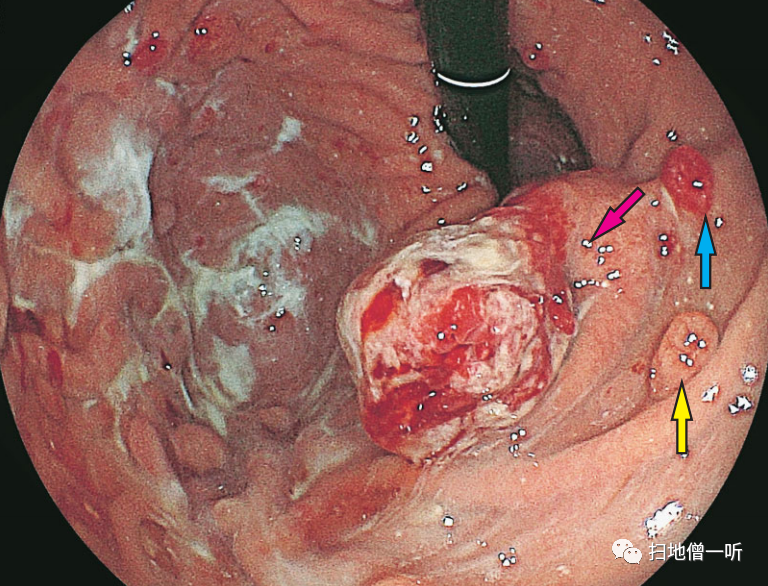

▼将P―CAB变更为PPI后,在第2周的内镜检查中确认了息肉的缩小。

▲在增生性息肉(红色箭头)的活检标本中,息肉表层的小凹上皮是增生性的,但是没有发现异型性。

▲在胃底腺息肉(黄色箭头)的活检标本中,确认了壁细胞的增生以及PCP样所见。

因使用PPI而发现胃增生性息肉增大的病例。通过投用PPI/P―CAB,贲门部的增生性息肉显著增大,使用Bonoprazan 20mg时,血清胃泌素值为2820 pg/ml,显示出显著的高值。将Bonoprazan变更为雷贝拉唑后,变更后2周内镜检查发现息肉缩小,血清胃泌素值降低到970pg/ml。在病理组织学上,在增生性息肉中发现了小凹上皮的显著增生性变化,但没有异型性。在附近的胃底腺息肉中,在组织学上发现了PCP样所见。